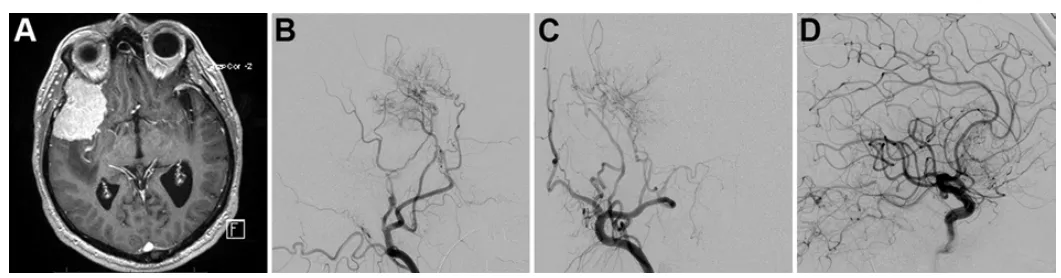

诺亚术前影像显示左侧岩斜区脑膜瘤,呈不均匀强化特征。

由于该肿瘤血供丰富,福教授在手术前进行DSA检查,显示其主要供血动脉为咽升动脉及脑膜垂体干。为降低后组颅神经损伤风险,选用弹簧圈栓塞技术。栓塞可减少术中出血、软化肿瘤质地,便于手术切除。

诺亚术前栓塞咽升动脉及脑膜垂体干。

矢状位MRI显示肿瘤经栓塞后血供部分阻断(部分去血管化)。